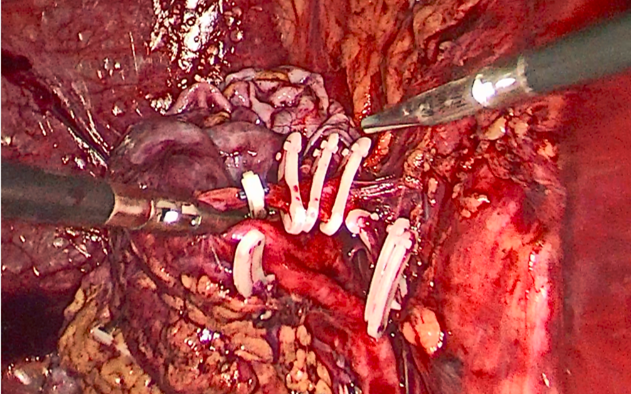

双侧输尿管切开取石术+双侧输尿管裁剪成型术,术中见上段输尿管因梗阻扩张似肠管,与周围脏器黏连明显,输尿管切开见结石周围包裹息肉,取石钳完整取出结石,双侧输尿管裁剪成型并留置内支架支撑。

正常人输尿管长约25cm左右,该患者输尿管迂曲扩张,长达35-40cm左右,裁剪部分输尿管成型